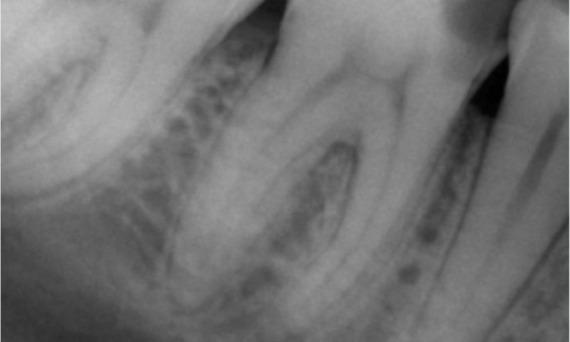

Önce: Muayenede, sağ alt ilk molar ile ilişkili çürük lezyonu mevcuttu. Radyografik incelemede lezyonun pulpa boynuzuna yakınlığı görüldü ve temel şikayet ile birleştirilince kronik geri dönüşümsüz pulpitis tanısı konuldu.

Sonra: Erişim kavitesi mümkün olduğunca konservatif olarak yapıldı. TruNatomy, genç hastanın yaşı nedeniyle tercih edilen sistem oldu. Dişin oklüzal yükün üstesinden gelme yeteneğini artırmak ve son restorasyonun ömrünü uzatmak amacıyla dentini mümkün olduğunca korumamız gerekiyordu.